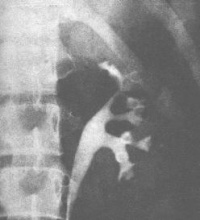

3.膀胱挛缩的诊断 在上述的症状以外,必需依靠X线检查。进行膀胱造影可以显示膀胱的外貌显著缩小。特别是延迟性膀胱造影还可观察到输尿管口的反流和对侧输尿管和肾盂的扩张积水(图4)。在检查的当时应注意膀胱有无急性炎症存在。膀胱有急性炎症存在时,一方面不适宜作膀胱造影,另一方面可以受到造影剂的刺激使膀胱收缩,造成膀胱挛缩的假象,故应予重视,以免误诊。